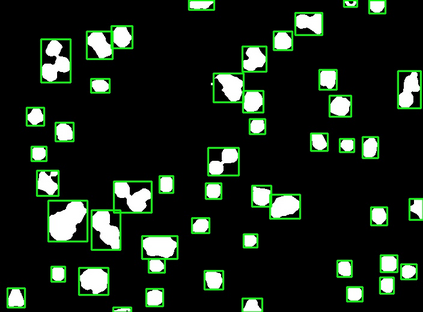

Bright-field microscopy, a cost-effective solution for live-cell culture, is often the only resource available, along with standard CPUs, for many low-budget labs. The inherent challenges of bright-field images -- their noisiness, low contrast, and dynamic morphology -- coupled with a lack of GPU resources and complex software interfaces, hinder the desired research output. This article presents a novel microscopy image analysis framework designed for low-budget labs equipped with a standard CPU desktop. The Python-based program enables cytometric analysis of live, unstained cells in culture through an advanced computer vision and machine learning pipeline. Crucially, the framework operates on label-free data, requiring no manually annotated training data or training phase. It is accessible via a user-friendly, cross-platform GUI that requires no programming skills, while also providing a scripting interface for programmatic control and integration by developers. The end-to-end workflow performs semantic and instance segmentation, feature extraction, analysis, evaluation, and automated report generation. Its modular architecture supports easy maintenance and flexible integration while supporting both single-image and batch processing. Validated on several unstained cell types from the public dataset of livecells, the framework demonstrates superior accuracy and reproducibility compared to contemporary tools like Cellpose and StarDist. Its competitive segmentation speed on a CPU-based platform highlights its significant potential for basic research and clinical applications -- particularly in cell transplantation for personalised medicine and muscle regeneration therapies. The access to the application is available for reproducibility